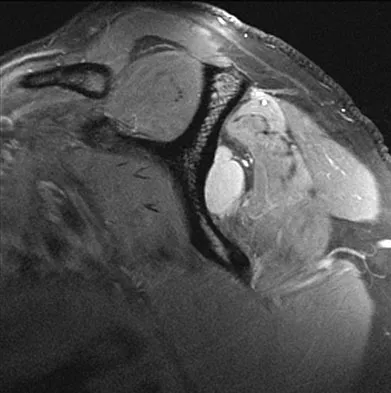

A 53-year-old man has had a long history of multiple joint symptoms, and he notes that the worst pain is from his left shoulder. A radiograph and MRI scan are shown in Figures 13a and 13b. Prior to surgical treatment of the shoulder, what is the most appropriate work-up?

Explanation